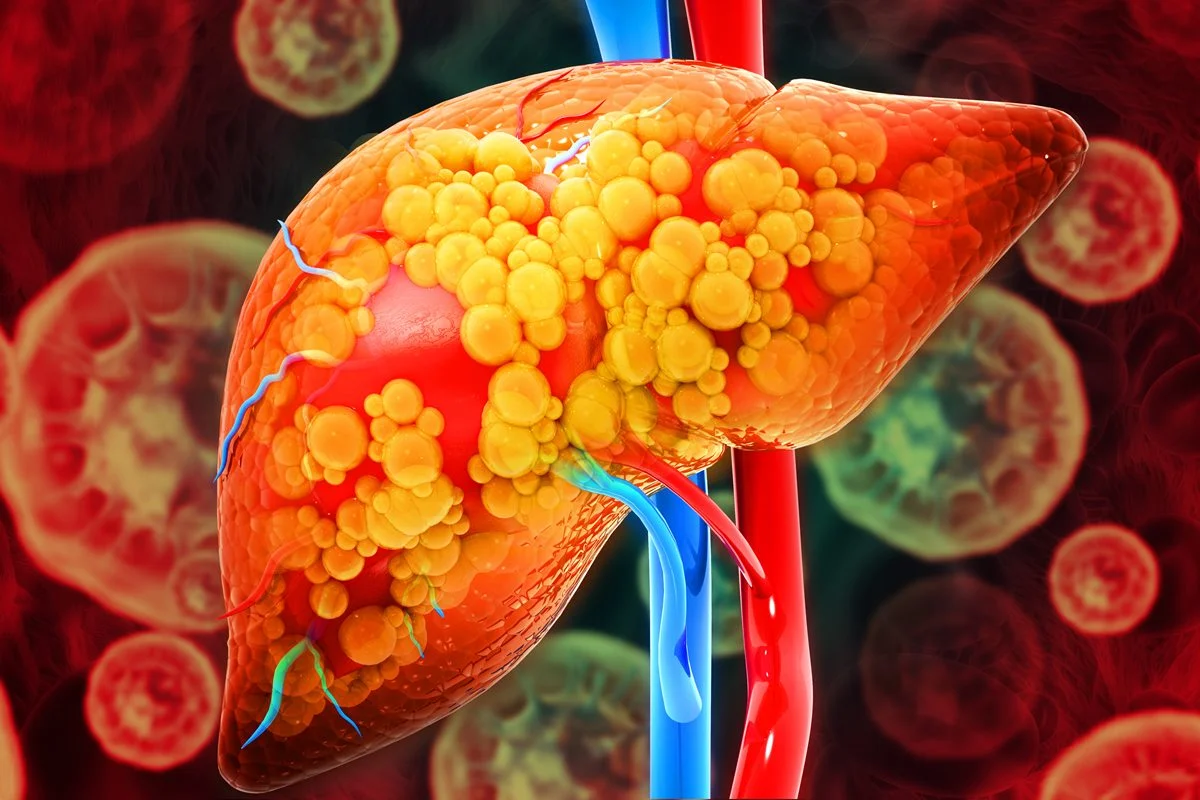

Estima-se que cerca de 30% da população mundial tenha um acúmulo de gordura no fígado chamado de esteatose hepática. A condição é típica de pacientes com dieta rica em gorduras e açúcares e sedentários, mas também pode estar relacionada à diabetes tipo 2, hipertensão e colesterol alto.

Em excesso, a gordura no fígado dificulta o trabalho do órgão, que filtra o sangue, elimina toxinas, metaboliza medicamentos, quebra a gordura, produz proteínas e regula a coagulação. No quadro, as células hepáticas ficam inflamadas, causam cicatrizes no órgão e podem desencadear ainda quadros graves de hepatite gordurosa, cirrose hepática e até câncer de fígado.

“Mesmo sem beber uma gota de álcool, o paciente com gordura no fígado pode desenvolver uma cirrose por esteatose hepática. A condição, por sua vez, é um fator de risco para hepatocarcinoma, que é o câncer que acomete o fígado. É importante tratar o quadro inicial para evitar doenças mais graves”, explica o médico Marcos Pontes, da Clínica Evoluccy, em Brasília.

- Popularmente chamada de gordura no fígado, a esteatose hepática acontece quando as células do órgão acumulam gordura em excesso.

- As principais causas estão relacionadas à obesidade, ao diabetes, ao colesterol alto e ao consumo excessivo de álcool.